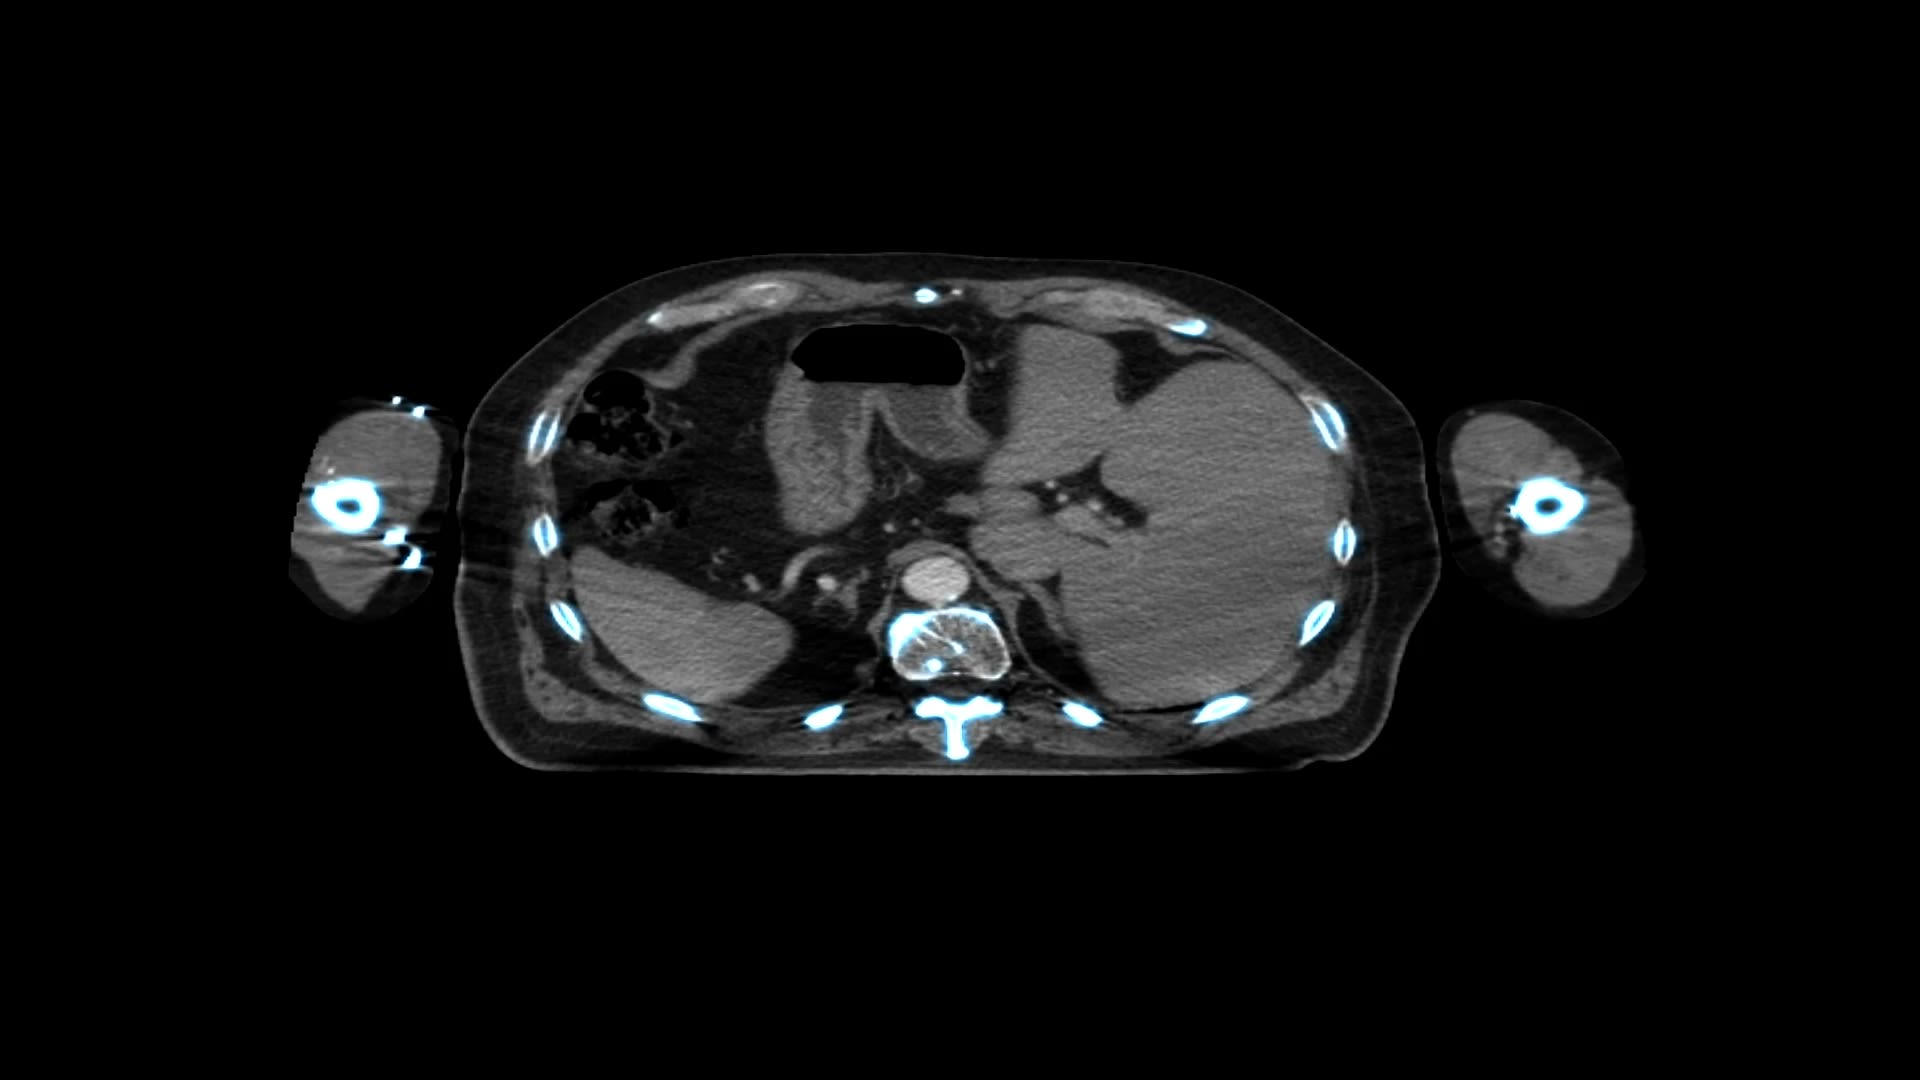

The last few decades have seen the evolution of conformal external beam radiotherapy (CRT), which uses computed tomographic (CT) images to precisely delineate a target, with X-ray beams from different directions targeting a tumour. Prior to this, radiotherapy beams were delivered using minimal image guidance as simple square or rectangular fields.

Conformal radiation therapy (CRT)

(Image credit: JazzIRT/Getty Images)

IMRT

Intensity-modulated radiotherapy (IMRT) is an extension of CRT, in which individual beams can be modified to produce doses of varying intensity, sculpting and shaping the beam to produce a concave shape. This reduces the dose and, consequently, the toxicity, to nearby normal tissues.

Intensity-modulated radiotherapy (IMRT)

(Image credit: Mark Kostich/Getty Images)

VMAT

Unlike IMRT, which uses multiple different beams of different intensities to produce an inhomogeneous dose distribution, volumetric modulated arc therapy (VMAT) can deliver dose continuously as the gantry of the linear accelerator (LINAC) rotates around the patient, hence reducing treatment time and minimising the overall dose. It is being increasingly used for everyday radiotherapy treatment and is especially useful when a tumour is next to a critical organ at risk.

Volumetric modulated arc therapy (VMAT)

(Image credit: Mark Kostich/Getty Images)